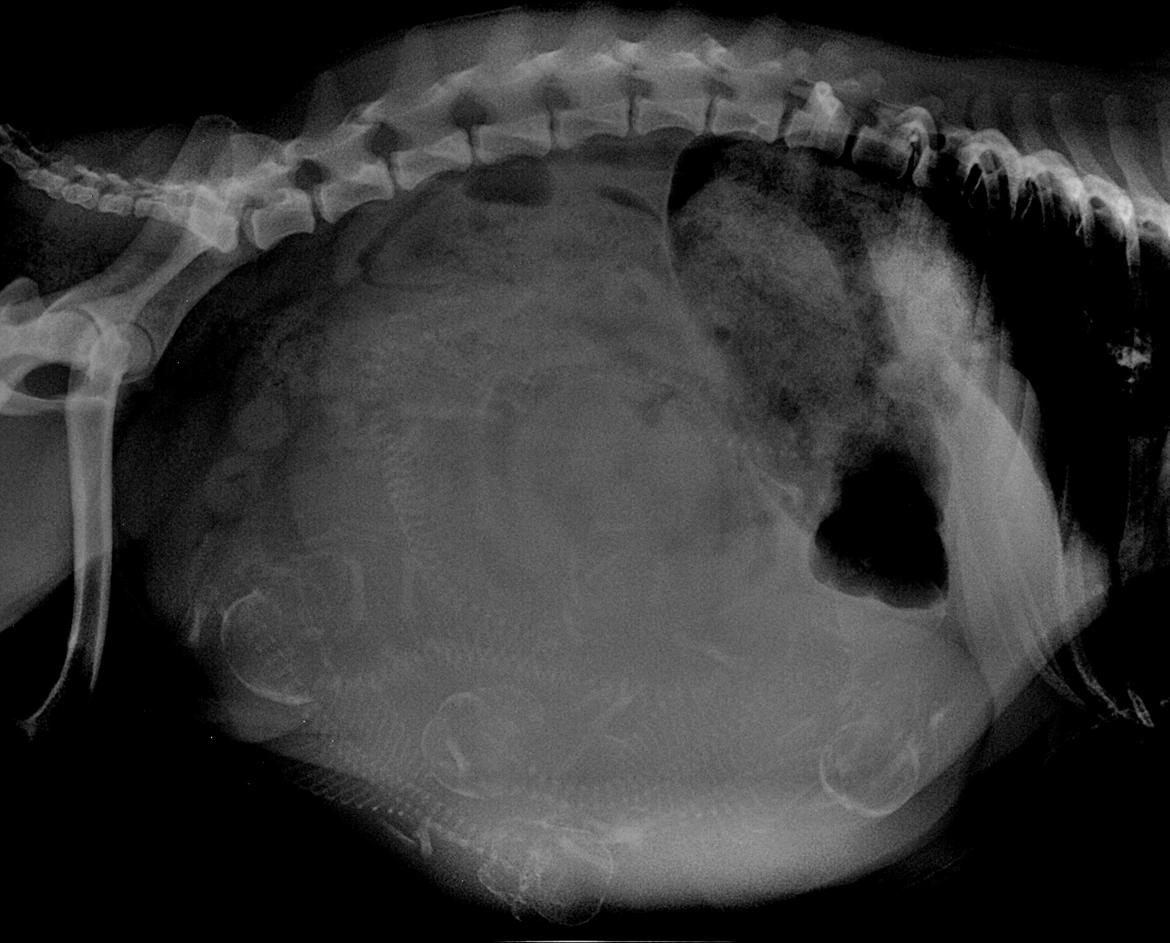

Mops Must Have Angelina Jolie - Røngtenbillede af Angelina's mave, fuld af hvalpe :) billede 18

Mops Must Have Angelina Jolie - En tyk mave <3 billede 19